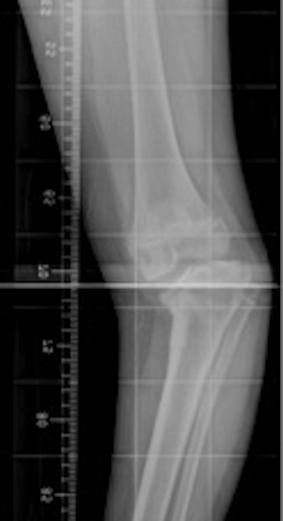

X-ray

Findings

- localised deformity at proximal tibia

Langenskiold Classification

Stage I: Beak 2-3 years

- irregular metaphyseal ossification

- medial metaphyseal beaking

Stage II: Saucer 2-4 years

- saucer shaped defect in medial metaphyseal beak

- medial epiphyseal wedging

Stage III: Step 4-6 years

- saucer deepens into step

- medial epiphysis irregular

Stage IV: Bent plate 5-10 years

- growth plate inclined distally at medial side

- i.e. epiphysis extends down over meta beak

Stage V: Double epiphysis 9-11 years

- Xray appearance of severe posteromedial depression

Stage VI: Medial physis ossified 10-13 year

- medial physeal closure